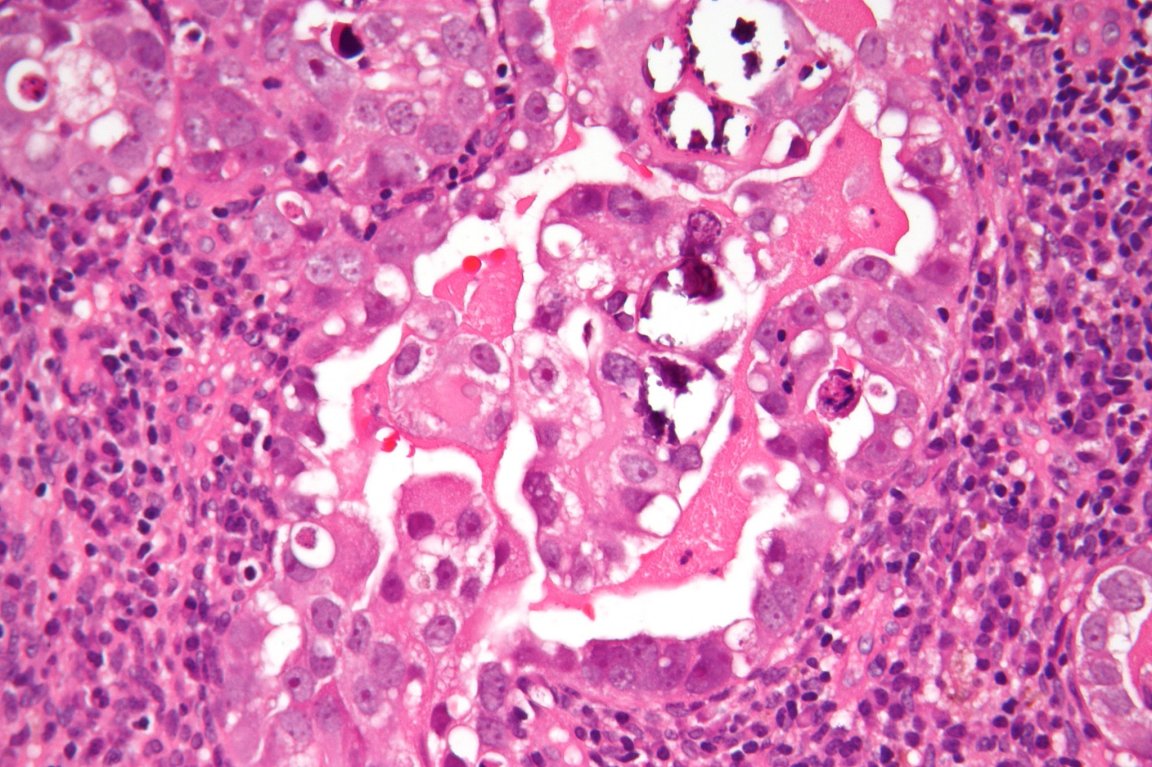

The treatment combines two anti-cancer drugs: paclitaxel is a type of chemotherapy designed specifically to treat endometrial cancer. The second, nintedanib (BIBF 1120), is a relatively new drug used to restrict blood vessel growth in tumors. It was this drug that was added to the nanoparticles. In this particular study, nintedanib was used to target tumor cells with a specific mutation: loss of function p53, which has been found to interrupt the life cycle of tumor cells, making them more resistant to chemotherapy.

Paclitaxel chemotherapy kills cells that are in the process of dividing (called mitosis), but cells with the Loss of Function p53 mutation slow this process down, making cancer more resistant to the chemotherapy treatment. This is where nintedanib comes into play. The drug targets cells with this mutation and forces them to divide so they can be more easily killed by the paclitaxel chemotherapy.